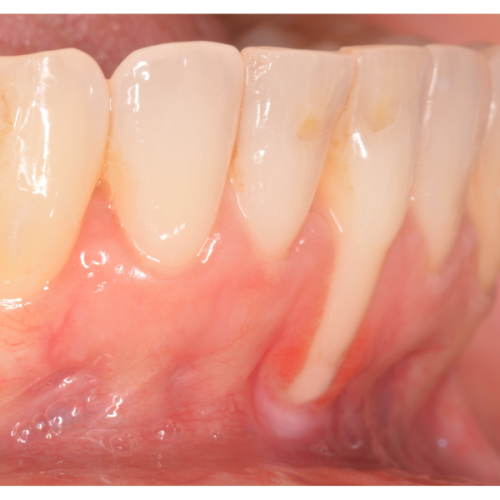

Cirugías de injertos

Existen cantidad de técnicas y biomateriales destinados a restauras los tejidos peridodos. Estos tejidos pueden ser tanto hueso como la encía que lo cubre. Se pueden reponer estos tejidos perdidos con injertos del propio paciente (autólogos) o con materiales sintéticos (biomateriales).